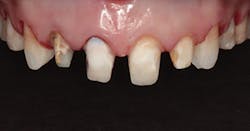

In Figure 1, you can see a close-up view of her smile as it was when she presented. She recently had noticed a fracture in both central incisor crowns and, since replacement was necessary, wanted to investigate the possibilities for improvement. The retracted facial view can be seen in Figure 2. Clinical and radiographic examination showed me that her overall dental health was good, with no periodontal disease or active caries. The patient expressed an interest in widening her smile and achieving a lighter color. The shade she desired was OM1 on the Vita Toothguide 3D-Master shade guide (figure 3).

Figure 2: Retracted facial view of the patient’s smile before treatment